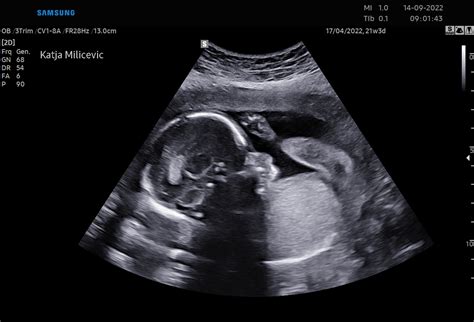

V 21. tednu nosečnosti otrok doseže velikost, primerljivo s korenčkom. Njegova povprečna dolžina od glave do pet je približno 21,6 cm, tehta pa okoli 340 gramov. Zanimivo je, da je v tem tednu plod že težji od posteljice. Njegov prebavni sistem se še naprej razvija in že deluje na poenostavljen način. Požiranje plodovnice, ki je hkrati tudi vir hranil za otroka, pripomore k razvoju prebavnega sistema.

Ob ultrazvočnem pregledu je zdaj mogoče videti številne otrokove dejavnosti, vključno s požiranjem in sesanjem palca. Pomemben razvojni mejnik tega tedna je, da se otrokov okušalni živec in brbončice že razvijejo do te mere, da otrok lahko okusi, kaj jeste vi. Okusi vaše hrane namreč pridejo v plodovnico, ki jo otrok nato zaužije. Kasneje bo otrok te okuse prepoznal, ko bo videl hrano na svojem krožniku.

Če pričakujete fantka, bo ultrazvok v tem tednu nadvse zanimiv. Videli boste lahko čudovite podrobnosti, kot so možganske poloble in srčni prekatki. Če pa pričakujete deklico, ima v maternici že vsa jajčeca, ki jih bo imela v življenju - in to približno šest milijonov! Trenutek, ko ugotovite ali gre za fantka ali deklico, je res vznemirljiv, lahko pa ta podatek ostane tudi presenečenje do poroda. Nekateri starši raje počakajo do rojstva. Morda lahko prosite zdravnika, da informacijo zapiše in jo shrani v kuverto, ki jo nato odnesete domov. Nato lahko pripravite zabavo, na kateri boste z družino in prijatelji razkrili presenečenje. Če nosečnost poteka brez zapletov, je to morda vaš zadnji ultrazvok, zato je pametno, da sedaj zaprosite za ultrazvočne posnetke.